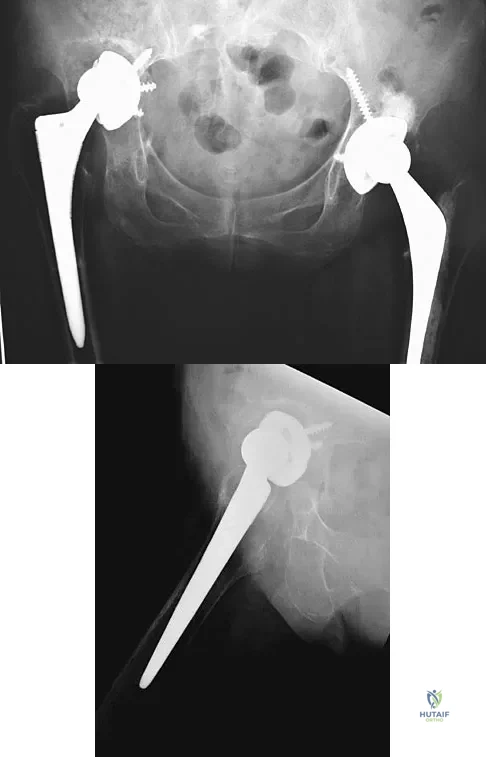

Question 43

A 72-year-old woman who underwent right total hip arthroplasty 7 years ago now reports right hip pain and limb shortening. Studies for infection are negative. AP and lateral radiographs are shown in Figures 13a and 13b. What is the most appropriate management?

Explanation